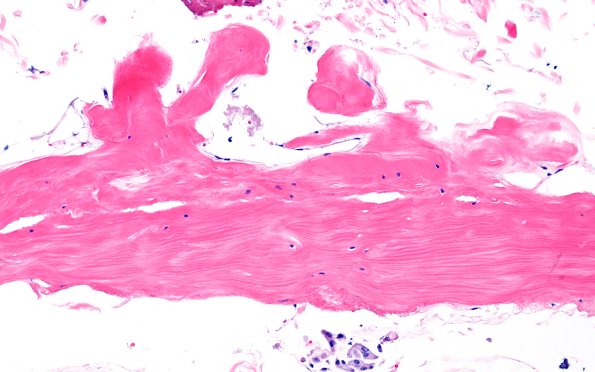

Arachnoid Fibrohyaline Plaques

9A2 Fibrohyaline plaque (Case 9) N11 H&E 20X A

Higher magnification of image #9A1. (H&E)